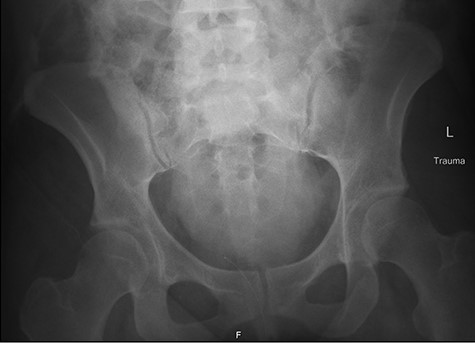

Left retrograde cystoscopy exhibiting extravasation of contrast.

Cystoscopy with retrograde pyelogram was performed by the urology team and this showed total disruption of the UPJ bilaterally with extravasation of contrast (Figs 3 and 4). She underwent bilateral interventional radiology nephrostomy tube placement. The definitive repair was planned for after pregnancy, but she required tube changes every 6 weeks. There was no fetal distress during her stay. She recovered well and was discharged after 5 days.